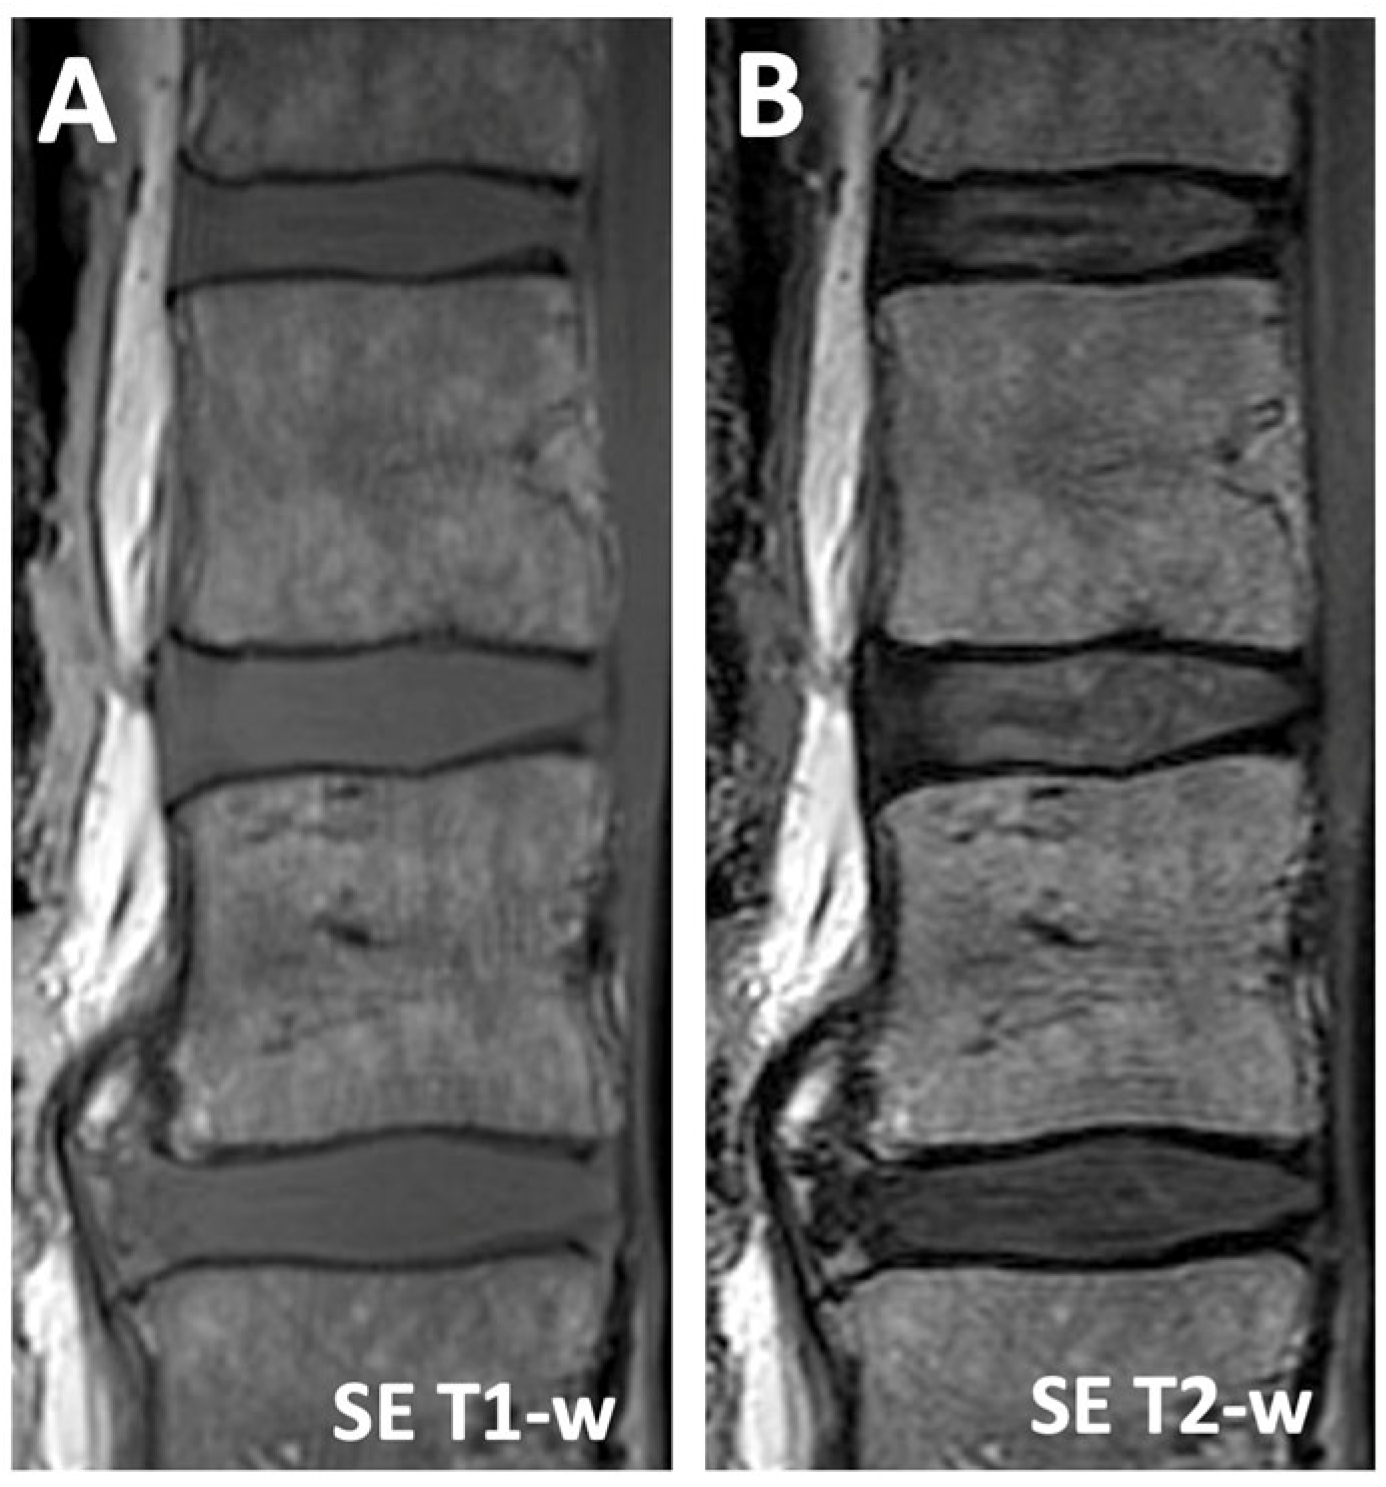

| SE T1-w | 650 | 10 | 12.4 (0.8) | 16.5 (4.1) | 10.2 (1.3) | −4.1 (4.2) | 2.2 (1.8) |

| SE T2-w | 3700 | 100 | 3.8 (1.0) | 7.9 (2.6) | 3.8 (0.9) | −4.1 (2.8) | 0.0 (0.9) |